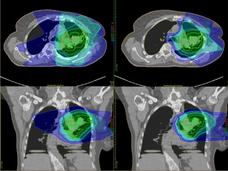

Is Proton Therapy Safer than Traditional Radiation?

Some experts believe that proton therapy is safer than traditional radiation, but research has been limited. A new observational study compared the safety and effectiveness of proton therapy and traditional radiation in adults with advanced cancer.